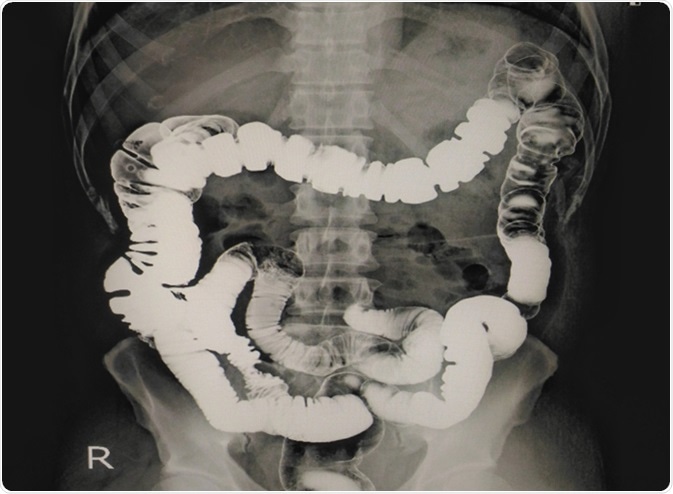

X-ray Barium enema showing normal colon mucosa. Image Credit: Richman Photo / Shutterstock